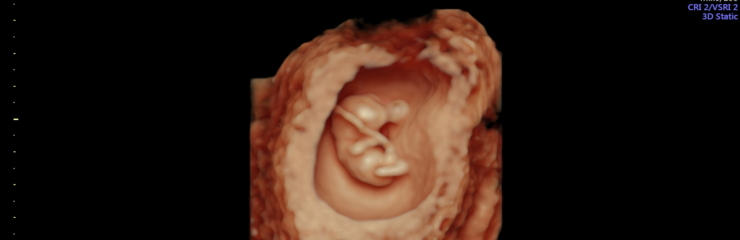

Плод:

На ультразвуковом исследовании плод уже виден.

В полости матки беременность диагностируется с начала 6-й недели (5+).

На 6–7-й неделе с помощью УЗИ можно определить сердцебиение плода и исключить внематочную или замершую беременность.

Раннее УЗИ (6–7-я неделя) важно и для диагностики пороков развития эмбриона.